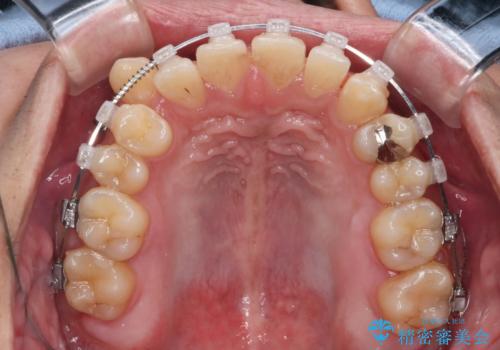

【クリア装置】八重歯とがたつきを綺麗に

- 上の八重歯と下の歯のがたつきを主訴に来院されました。

矯正検査の結果、抜歯はせずに

臼歯を遠心移動させ、歯列をワイヤーで整えることでスペースを確保し、IPR(歯と歯の間を削る処置)を加えて歯並びを綺麗にする治療計画を立てました。

歯の移動にオープンコイルとMI(歯肉に埋入するネジ)を用いました。

非抜歯矯正だったこともあり、1年半以内という短い期間で矯正を終了することができました。

気にされていた八重歯とがたつきが綺麗に改善されました。